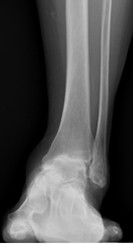

人工足関節置換術

術後レントゲン写真